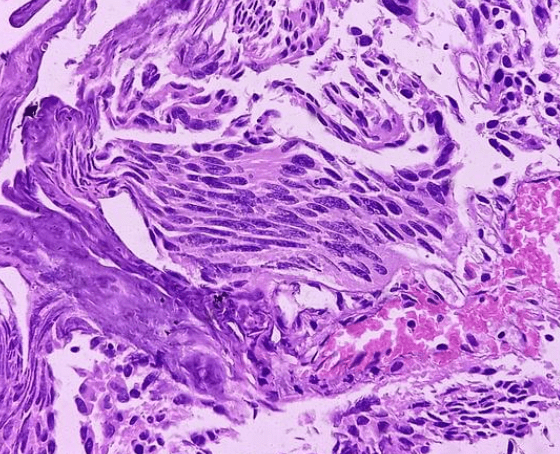

In rare cases, the tumor mass may be palpable, particularly in advanced metastatic stages. Routine blood tests generally do not show significant tumor-related abnormalities. Urinalysis typically reveals substantial hematuria, but again, this may not offer definitive clues pointing to cancer. Imaging techniques can be highly beneficial for diagnosis. Ultrasound is commonly used, and in cases where ultrasound is insufficient, CT scans and cystoscopy become crucial diagnostic tools. A definitive diagnosis is made through biopsy, which can be obtained via cystoscopy or surgical procedures. Staging the tumor is vital, and close communication with pathologists is essential during this phase.